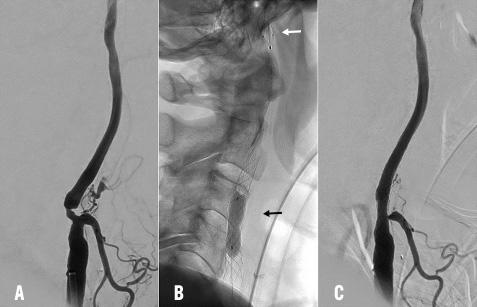

Ces résultats sont résumés dans les tableaux 1 et 2. La figure 1 montre un exemple de traitement par stenting carotidien.

Fig 1

Angiographie conventionnelle montrant une sténose à l’origine de la carotide interne avant et après traitement par stenting

A. Sténose de la bifurcation carotidienne qui s’étend jusqu’à l’origine de la carotide interne avec un rétrécissement supérieur à 70 % ; B. Mise en place d’un stent, suivi d’une angioplastie intra-stent (flèche noire) sous protection d’un filtre distal (flèche blanche) ; C. Résultat après le stenting qui montre l’absence de sténose résiduelle.